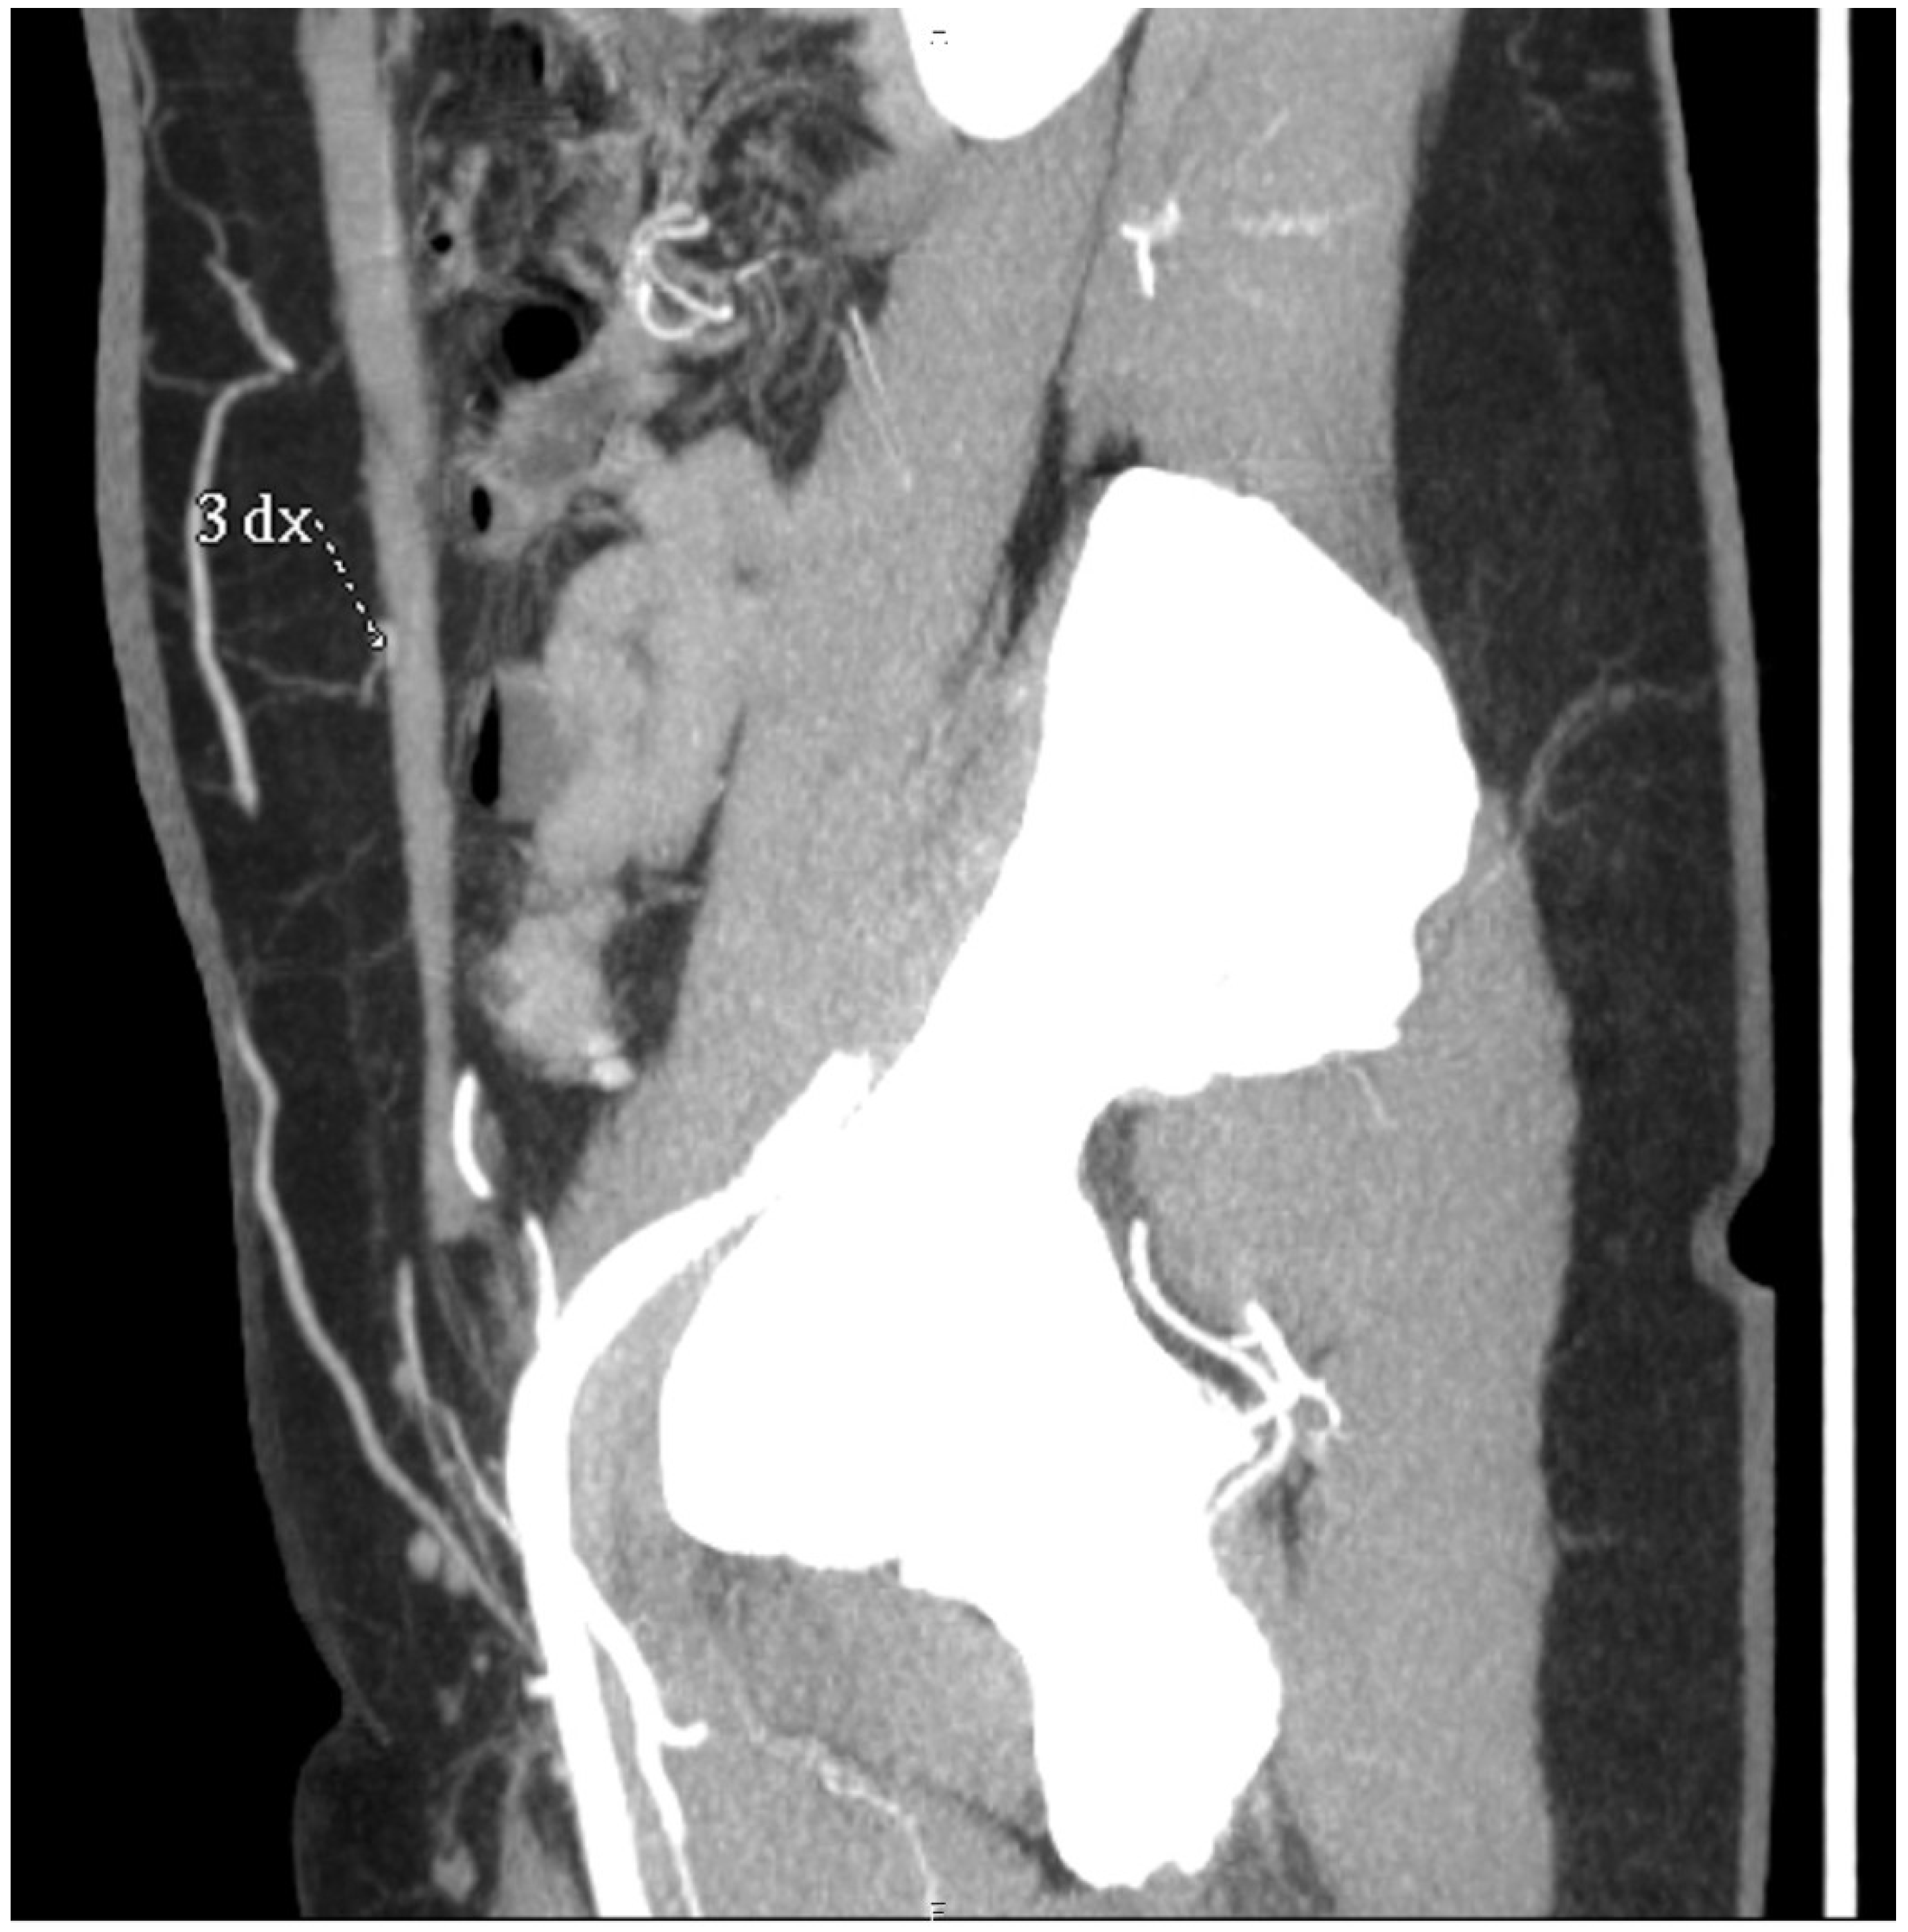

Figure 5. Sagittal sections of preoperative CTAs in the venous phase, showing the superficial venous system. The superficial inferior epigastric vein (SIEV) is clearly visualized.